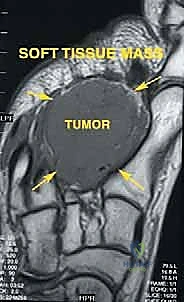

3. الأورام الخبيثة (ساركوما العظام والأنسجة الرخوة)

عند ظهور أورام سرطانية في مقدمة أو منتصف القدم، يتطلب الأمر استئصالاً جذرياً مع هوامش أمان واسعة لضمان عدم عودة الورم. يتيح بتر شوبارت أو ليزفرانك إزالة الورم بالكامل مع تجنب بتر الساق.